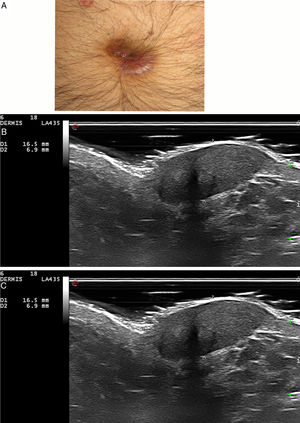

Five patients (six lesions) (four men and one woman) with a median age of 67 years (range, 39-71) and a biopsy-proven GF were included. In three of patients the lesions were located on the face, one on the scalp, one on the ear and one on the umbilicus. Most patients had undergone several treatments without clinical improvement (Table 1). On ultrasonographic evaluation, GF presented in all patients as a hypoechoic and heterogeneous lesion in dermis and hypodermis with an increased vascularity on color Doppler mode (Fig. 1–2). Almost all lesions (5/6) were ill-defined. In 5/6 GF a marked subepidermal hypoechoic/anechoic band was observed. One lesion (case 5, nose) presented a posterior enhancement. There were no significant differences in ultrasound characteristics between facial and extrafacial GF (Table 1).

Characteristics of patients with granuloma faciale.

| Case n | Sex/age (years) | Time of evolution (years) | Anatomic location | Previous treatments | Histological description | Ultrasound features (B-mode ) | Doppler mode |

| 1 | m/39 | 5 | right cheek | topical corticosteroids, hydroxycloroquine, dapsone, laser, topical tacrolimus | Presence of Grenz zone. Dense inflammatory infiltrate constituted mainly by eosinophils, few histiocytes, lymphocytes and occasional plasma cells. | Hypoechoic, heterogeneous and ill-defined lesion in dermis and hypodermis. | Increased vascularity |

| Subepidermal hypoechoic band | Vessels in dermis up to 0.63 mm in diameter. | ||||||

| Umbilicus | topical and intralesional corticosteroids, topical tacrolimus, hydroxycloroquine | Presence of Grenz zone. Dense lymphoplasmocytic inflammatory infiltrates in dermis. | Hypoechoic, heterogeneous and well-defined lesion in dermis and hypodermis. | Increased vascularity. | |||

| Subepidermal hypoechoic band | Vessels in dermis up to 1.4 mm in diameter | ||||||